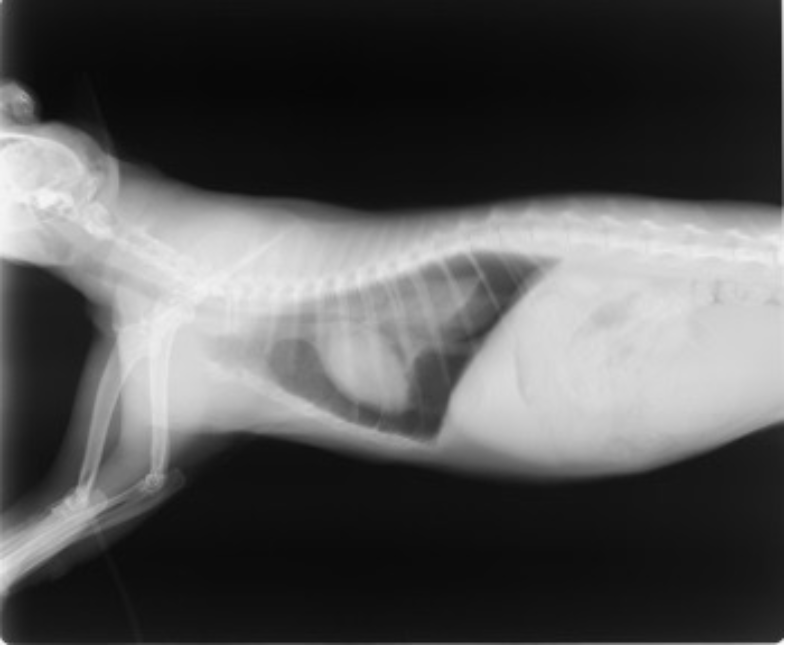

หลังจากการตรวจร่างกายพบว่ามีภาวะหายใจลำบาก ใช้ช่องท้องช่วยหายใจ หายใจถี่ นั่งยืดคอ นอนไม่ได้ หัวใจเต้นเร็ว ปีกจมูกขยับ ไม่อ้าปากหายใจ เบื้องต้นจึงได้ปรับสภาพด้วยการให้ออกซิเจน หลังจากนั้นจึงได้นำน้องกีตาร์ไปเอกซเรย์พบภาวะโพรงเยื่อหุ้มปอดมีอากาศ (pneumothorax) ไม่พบการแตกหักของกระดูกซี่โครง หรือตำแหน่งอื่นๆ ไม่พบแผลอื่นๆภายนอกร่างกาย

ภาพถ่าย x-ray